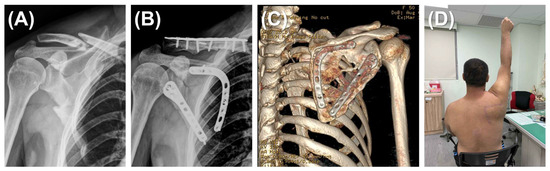

Figure 2. Dual plating for scapular fracture. (A) A 52-year-old man presented with a left scapular fracture (AO/OTA 14B type) and an ipsilateral clavicle fracture. The scapular body exhibited comminution along both the medial and lateral borders. (B) Through a modified Judet approach, the scapular fracture was reduced and stabilized using dual plating (lateral and medial borders). The clavicle fracture was addressed with a standard fixation procedure. (C) A 3D reconstruction at the 16-month postoperative follow-up, after removal of the clavicular implants, demonstrating successful osteosynthesis of the scapular body fracture without malalignment. (D) Clinical photograph of the 52-year-old man at 12 months demonstrating restoration of full active shoulder abduction.